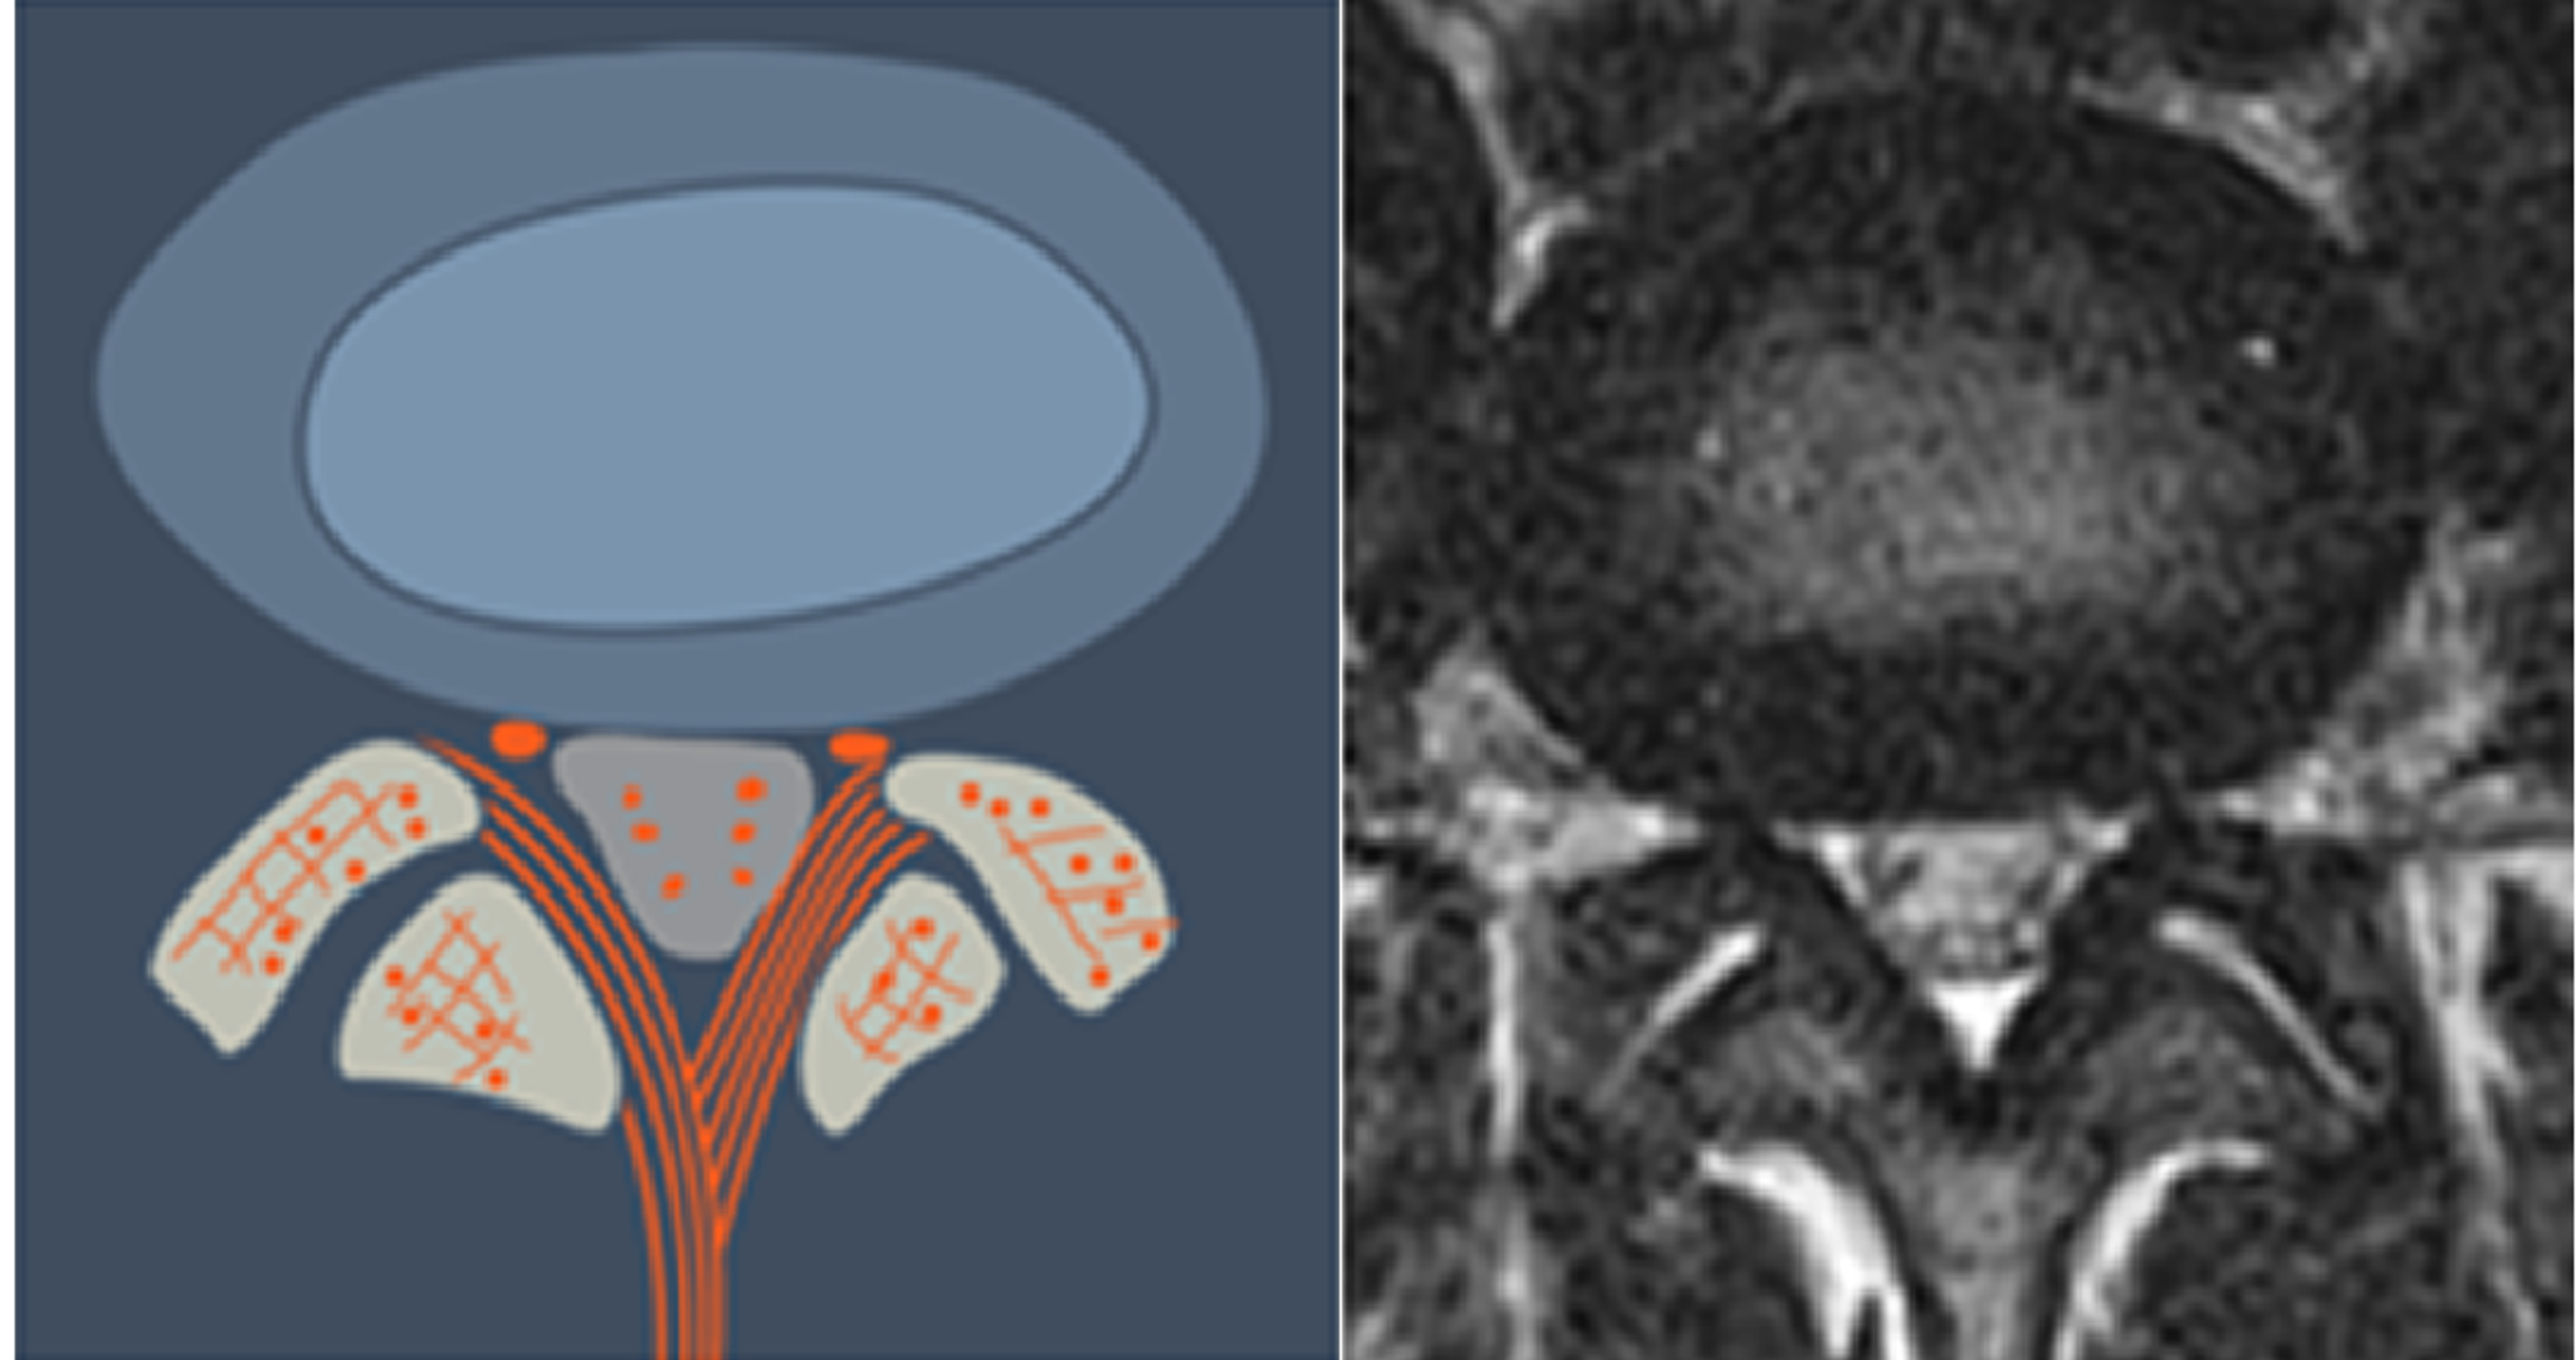

Lumbar Disc Herniation (a) Showing herniated disc at L4/L5 level [14 Disc Bulge Classification The article provides a discussion of the recommended diagnostic categories pertaining to the lumbar disc:. bulging disc the presence of disc tissue extending beyond the edges of the ring apophyses, throughout the. the article provides a discussion of the recommended diagnostic categories pertaining to the lumbar disc: Annular tissue projects beyond the margins of the adjacent vertebral bodies,. Disc Bulge Classification.